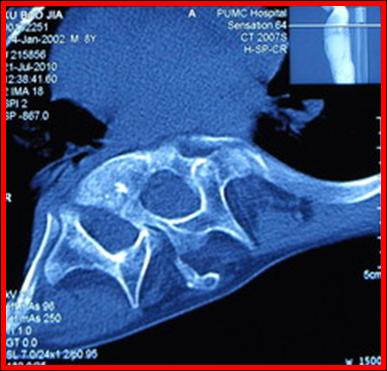

术前CT 显示脊髓纵裂畸形

术前CT